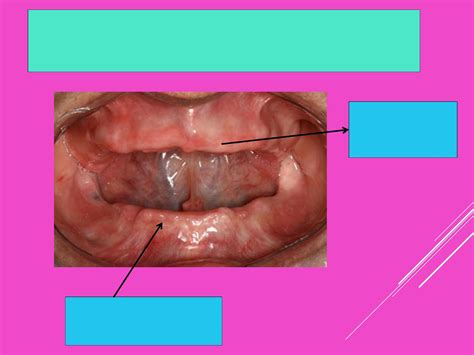

Caso 2: Arcada Completa Desdentada

SE TRATA DE UNA PACIENTE DE 76 AÑOS desdentada en el maxilar superior. En un primer momento, se colocó la mínima cantidad anestésica en la zona vestibular permitiendo estabilizar la férula muco-soportada con los pines de anclaje por vestibular. Al colocar solo anestesia en esa zona, se evitó engrosar los tejidos blandos, interfiriendo en el correcto asentamiento de la férula (Raico-Gallardo y cols. 2017). Tras estabilizar la férula, se marcó con la fresa del punch y un lápiz tinta la posición de los implantes a través de la férula quirúrgica, se retiró la férula y se midió la cantidad de encía queratinizada en la zona vestibular.

Cuando hay menos de 3 mm se eleva un colgajo de espesor completo llevando la encía queratinizada hacia vestibular, entre 3 y 5 mm se realizan minicolgajos, y si hay más de 5 mm se utiliza una técnica flapless con punch. En este caso clínico había suficiente encía queratinizada para realizar una técnica mínimamente invasiva, por lo que se reforzó la técnica anestésica por palatino, se eliminaron con el punch los tejidos blandos y se reposicionó la férula para colocar 6 implantes de cuello convergente de forma totalmente guiada a través de la férula quirúrgica aprovechando el hueso remanente.

Una vez colocados se tomaron las impresiones digitales con el escáner intraoral, se utilizó la prótesis completa de la paciente para, junto con imágenes 2D, colocar una prótesis de carga inmediata CAD-CAM utilizando un flujo digital. A los 3 meses se empezó a conformar los tejidos blandos dando espacio a las papilas y modificando el perfil de emergencia de la prótesis provisional para conseguir un engrosamiento de los tejidos blandos periimplantarios.